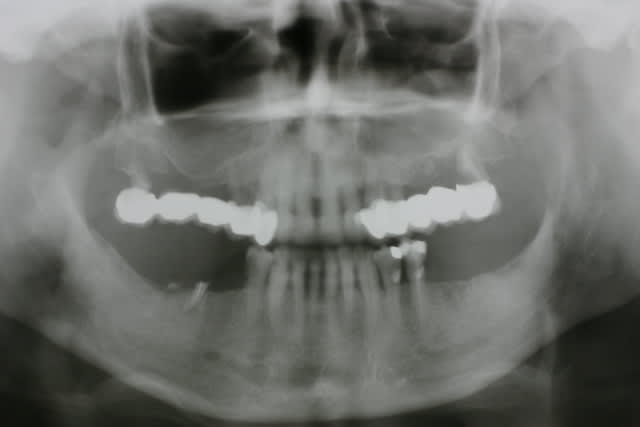

On ne dirait pas la même crête et pourtant il s agit bien de la patiente en préop et 18 mois plus tard...

Quel changement de volume et de qualité tissulaire...

qd tu vois la transformation tissulaire au niveau du volume et de la qualité des muqueuses avant-après, je doute très fort que ce soit une muqueuse diapneusique comme tu le laissais entendre...

A quoi attribues-tu ce changement de volume de tissus ?

C'est uniquement le nanobone ?

J ai placé 2 x 1.2ml et un dernier flacon de 0.6ml

3ml en tout

C est pas un kilo qd même :-)))))))))